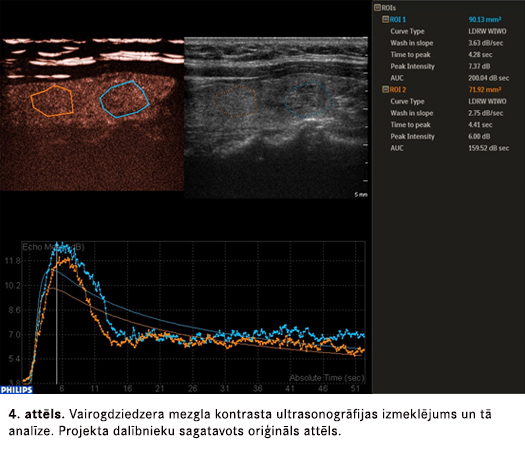

Latvijā vairogdziedzera mezglu izvērtēšanai plaši tiek izmantota ultrasonogrāfija, turpretim kontrasta ultrasonogrāfija, izmantojot mikroburbuļus saturošu aģentu, vairogdziedzera audzēju diagnostikā līdz šim mūsu valstī netika izmantota. Pētījuma ietvaros ne tikai gūta Latvijā pirmā pieredze vairogdziedzera kontrasta ultrasonogrāfiskajos izmeklējumos, bet arī zinātniski analizēti iegūtie attēldiagnostikas dati, tostarp tādi inovatīvi parametri kā mezgla vaskularizācija kontrasta ultrasonogrāfijas izmeklējumā, tās homogenitāte, kontrastvielas izvade no mezgla un līknes, kas atspoguļoto signāla intensitātes izmaiņas laikā. Rezultāti būs starptautiski vērtīgi – tie palīdzēs citu valstu radiologiem interpretēt gūtos datus un plānot tālākos pētījumus.

Projekta rezultātā endokrīnos un neiroendokrīnos audzējos izpētīta šūnu proliferācijas aktivitāte un to regulējošie multiplie molekulārie faktori, šūnu adhēzija un tās izzudums, šūnu plasticitāte jeb iekšējā „karkasa” izmaiņas, cilmes šūnu marķeri. Salīdzinot pētīto proteīnu ekspresijas līmeni audzējos ar veseliem audiem, kā arī pētot šo marķieru saikni ar audzēja spēju augt invazīvi un izplatīties organismā, konstatētas būtiskas likumsakarības. Molekulāro marķieru analīze ar imūnhistoķīmiskās vizualizācijas un datormorfometrijas metodēm sistematizēta diagnostiskā algoritmā. Vairogdziedzera audzējos atklātas vaskularizācijas īpatnības, kuras izvērtējamas ar kontrasta ultrasonogrāfijas metodi un arī iekļautas diagnostiskajā algoritmā.